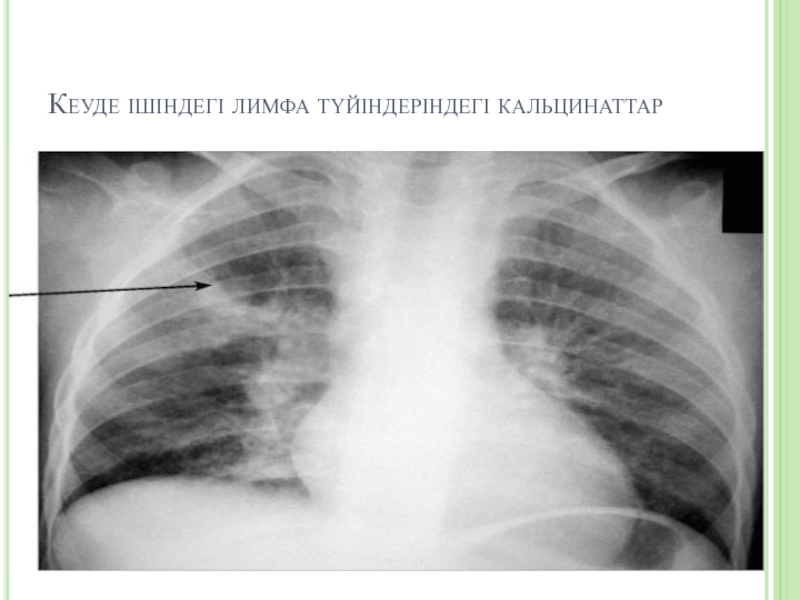

Слайд 21Кеуде ішіндегі лимфа түйіндеріндегі кальцинаттар

Кеуде ішіндегі лимфа түйіндеріндегі кальцинаттар